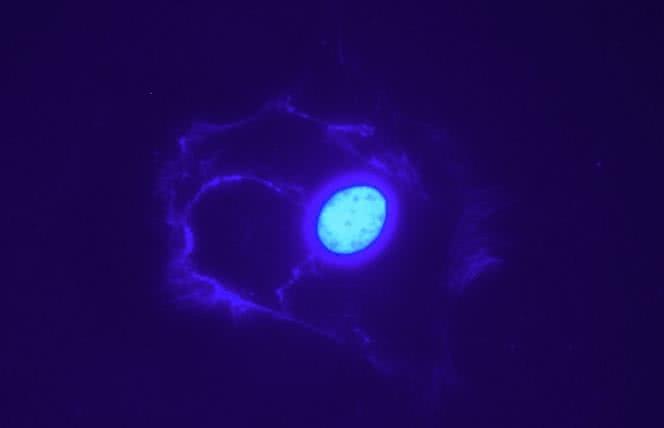

Czego jeszcze nie wiesz o mitochondriach?

Mitochondria, drobne struktury wewnątrz komórki, nie przestają nas zaskakiwać.